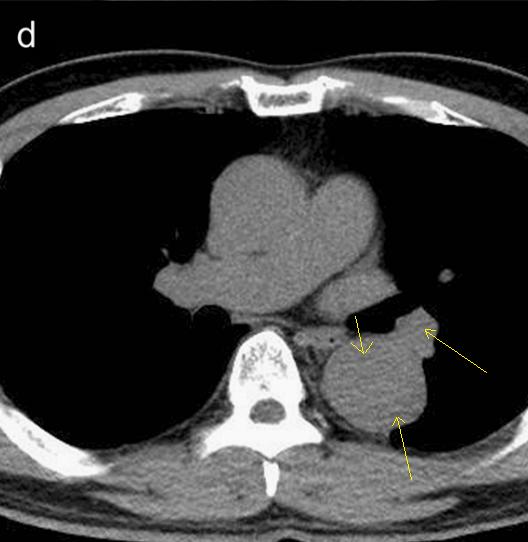

下图的胸部CT平扫,有什么致命的问题?

图7

仔细一看,主动脉里面有线样阴影!并且,线样阴影两边的密度一高一低!

图8

增强CT一看,主动脉夹层,密度相对高的是流动的血液!

图9